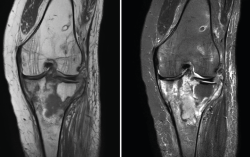

4. Lesiones isquémicas

4.1. Necrosis avascular (NAV)

En la NAV (aséptica, isquémica u osteonecrosis), hay una pérdida del flujo de sangre en el tejido óseo que hace que el hueso muera.

Se produce por un trastorno de la irrigación sanguínea o por lesiones celulares en el hueso y en la médula ósea.

Puede observarse en la RM la disminución de la intensidad de la lesión mucho antes de que se aprecie con otras pruebas diagnósticas (Figura 51).

Figura 51. Corte de secuencia T2 Fat-Sat coronal: lesión osteocondral con necrosis avascular del fragmento óseo.

4.3. Osteocondritis

En la osteocondritis se aprecia una lesión subcondral caracterizada por resorción ósea, colapso y la formación de un secuestro.

El estudio por RM es una herramienta valiosa para diagnosticar e identificar las lesiones del cartílago. Conocer el aspecto del cartílago y saber cuánto y cuándo se lesiona, basándose en las clasificaciones actuales, permiten al radiólogo proporcionar la máxima información al clínico(20).

Figura 53. Corte de secuencia sagital (A) y axial (B) T2 Fat-Sat de RM de rodilla: lesiones osteocondrales en el fémur y la rótula.

Numerosos estudios demuestran la utilidad de la RM para definir la estabilidad o inestabilidad de la lesión en la osteocondritis, destacando su carácter no invasivo y la capacidad de valorar la progresión y la respuesta al tratamiento(21)(Figuras 53 y 54).

Figura 54. Corte de secuencia T1 y T2 Fat-Sat coronal de resonancia magnética: gran osteocondritis en el cóndilo femoral interno con edema en la medular adyacente.